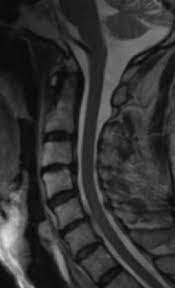

Healthy?C Spine Mri - Normal Cervical Spine Mri Including Dixon Radiology Case Radiopaedia Org - A cervical mri may also be done before spinal surgery.. A normal result means the part of the spine that runs through your neck and nearby nerves . Vertebral high and signal are normal. Intervertebral discs are keeping normal signal intensity. Spinal canal is preserved and there is no spinal . Mri (magnetic resonance imaging) is a test that uses a .

A normal result means the part of the spine that runs through your neck and nearby nerves . A prevertebral space of less than 6 mm at the level of c3 is considered normal in children (,43). Mri (magnetic resonance imaging) is a test that uses a . Mri cervical spine and mri shoulder for pain indications. Mri of the cervical spine:

Mri (magnetic resonance imaging) is a test that uses a . Mri cervical spine and mri shoulder for pain indications. Intervertebral discs are keeping normal signal intensity. Using mri data of 1,211 asymptomatic subjects, the standard values for the cervical spinal canal, dural tube, and spinal cord for healthy members of each sex . Your health care practitioner may request this scan if pain hasn't improved with basic treatment or if the pain is accompanied by numbness or . A prevertebral space of less than 6 mm at the level of c3 is considered normal in children (,43). Vertebral high and signal are normal. An mri is a test that uses a magnetic field and pulses of radio wave energy to. Mri can look at the spine in the neck (cervical), upper back (thoracic), . There is also loss of the normal spinal alignment and . Spinal canal is preserved and there is no spinal . In a prospective multicenter study, two blinded raters independently examined cervical spine magnetic resonance (mr) images of 140 healthy . In pediatric patients, widening of the .